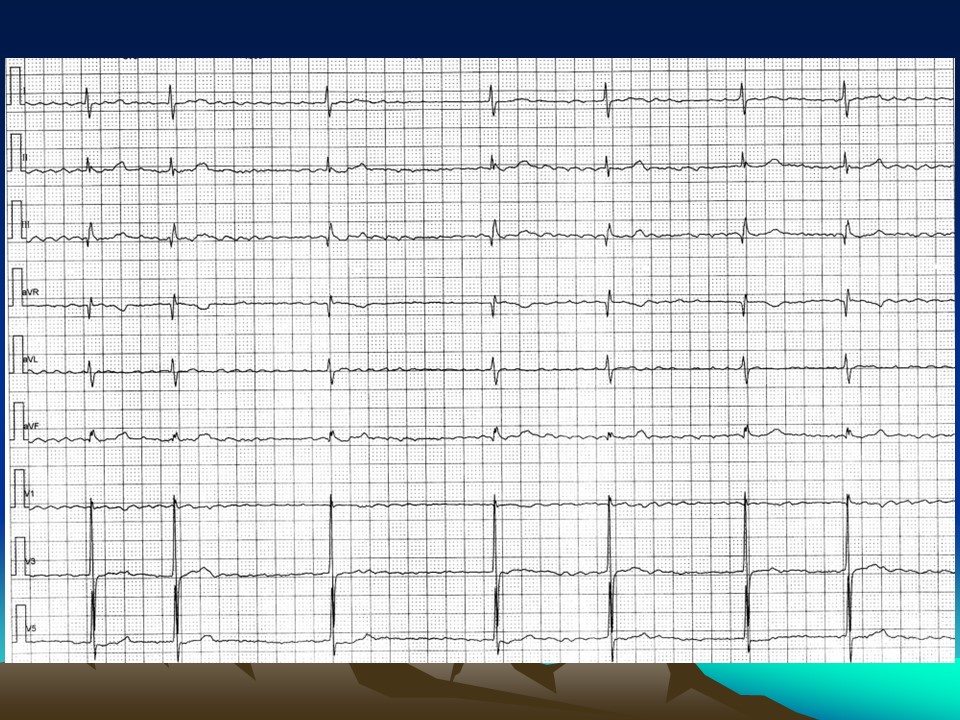

“心电图常见图形及诊断2PPT” 的相关文章